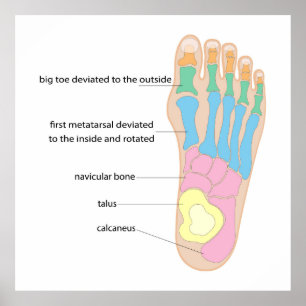

Structure of the human foot poster

PriceCA$107.00